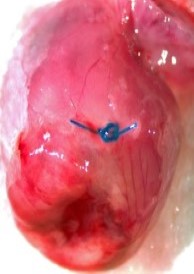

LAD Reperfusion Model: 30 Minute Ischemia with 2 Hour Reperfusion

Pictured: Cardiac Perfusion With Evans Blue Dye To Define Infarct zone.

4-7 Days Post MI Average 30% Infarct Area. Model Developing Athero